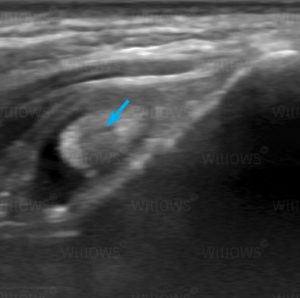

Ultrasound scanning provides a moving ‘real time’ image, a bit like an instant movie of what the probe is ‘seeing’. This allows assessment of movement in the heart or other structures in the body, it also enables the Imaging Specialist to ‘piece together’ the images in their mind as the probe is moved around. Movement of blood in the heart and blood vessels, as well as in organs, can also be assessed. Real time imaging also allows the Imaging Specialist to take samples (biopsies) of different tissues under ultrasound guidance, where the sampling needle can be directly visualised with ultrasound in the tissues at the time the sample is being taken.

The majority of ultrasound scans performed at Willows are of the abdomen. Ultrasound provides superb detail about the internal structure of the organs, and differentiates between fluid and solid tissue. It is invaluable when there is abnormal fluid (called ‘ascites’) within the abdomen. In addition, ultrasound allows assessment of movement in real time, and so stomach and gut movement can be seen. Sampling of the different tissues and fluids within the abdomen can be performed with increased safety under ultrasound guidance, rather than being carried out ‘blind’. Below is a video of an ultrasound scan of urine entering the bladder. The urine enters the bladder via the tubes from the kidneys (the ureters) and it can be seen squirting into the bladder as the red coloured jet (on this Doppler colour-flow scan the red colour indicates a rapid flow of fluid.